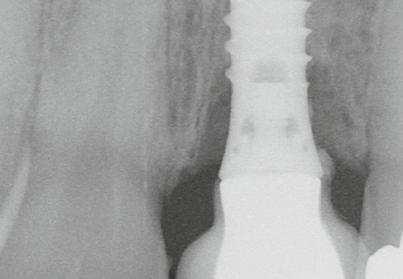

6. ábra: Klinikai helyzet a kezdeti vizsgálat során. 9 mm mély periimplantáris szondázási mélység, szondázási vérzéssel. Az arc periimplantáris nyálkahártyáján sinus felőli szivárgás figyelhető meg. A periimplantitis diagnózisának felállítása előtt körülbelül 4 évvel, amikor a pácienst kezelésre utalták, cementált fogpótlást helyeztek el ezen a Straumann lágyrész-szintű implantátumon.

7. ábra: Röntgenfelvétel a marginális csontszintekről az implantátumnál a kezelés előtt. Meziális és disztális csontvesztés figyelhető meg, amely az implantátum második menetéig terjed. Figyelje meg az implantátum disztális felszínén lévő radioopak anyagot (felesleges rögzítőcement)! Figyelje meg a 11-es fog meziális felszínén lévő fogkövet is!